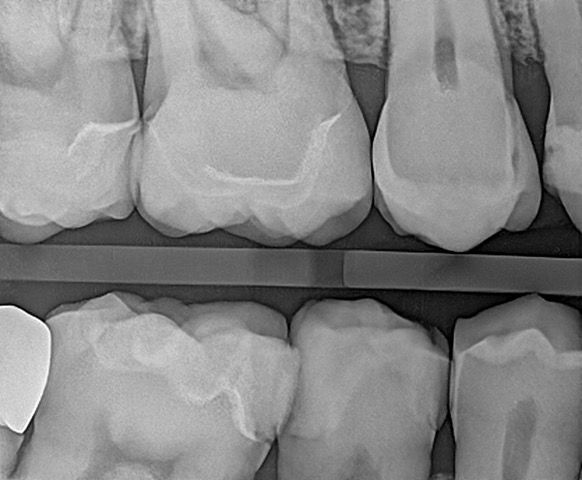

In my own practice, I compared two bitewings from the same patient, one taken with Acuity and one with our existing sensor, using identical exposure settings. The Acuity image immediately stood out. It showed noticeably sharper definition, cleaner contrast, and clearer interproximal visibility. The improvement was visible at a glance and reinforced the diagnostic advantages reported by our evaluators. This kind of image sharpness saves time and reduces retakes.